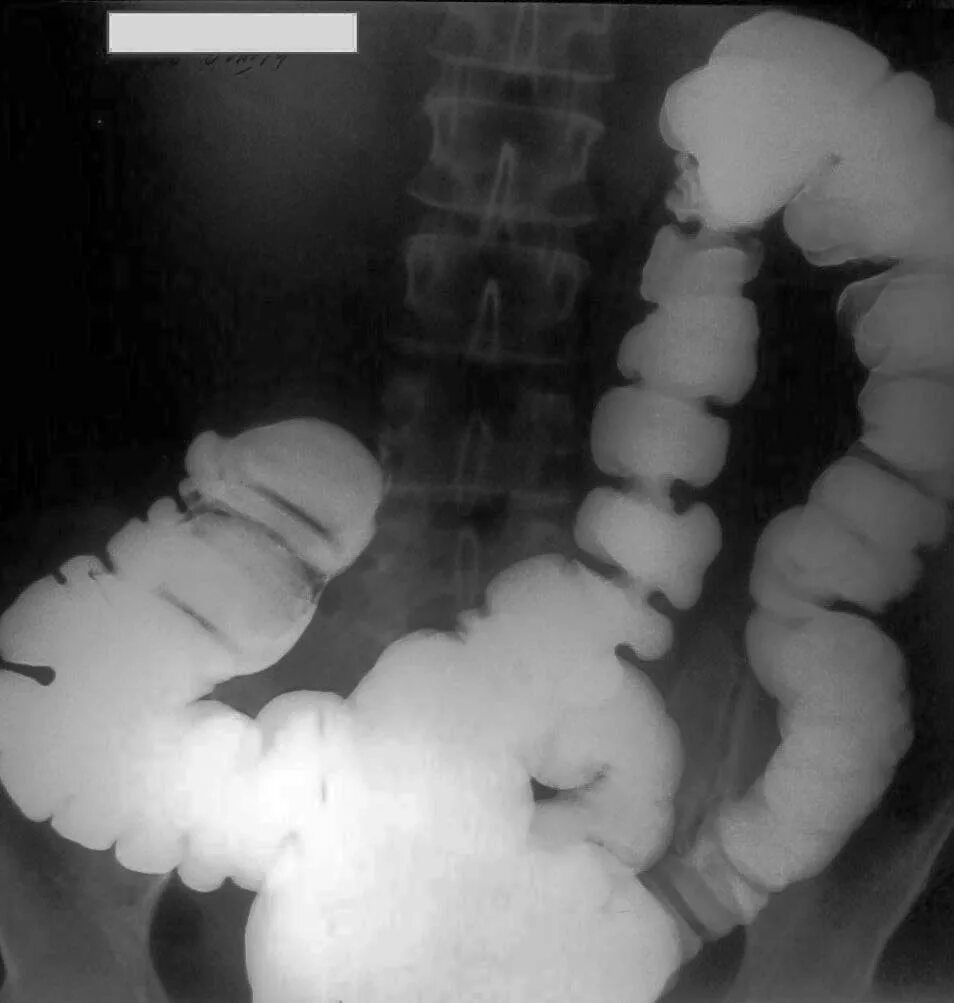

Кишечник после ирригоскопии